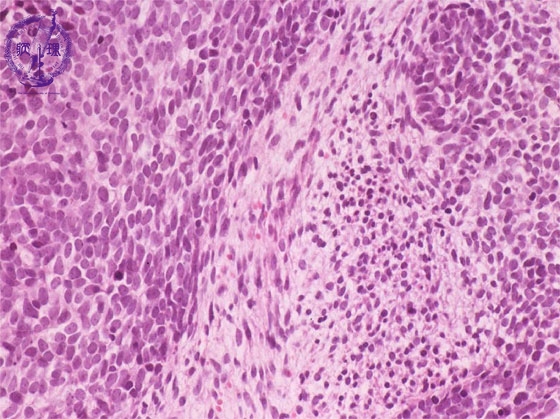

- (16)Nephroblastoma (Wilms tumor)

Microscopic findings ( HE, high power view): The blastemal element (red dotted lines) is composed of small, homogenous and immature tumor cells with scanty cytoplasm. In the stromal element, tumor cells are spindle in shape and loosely arranged (blue dotted line).

Click the image to see the enlarged image.